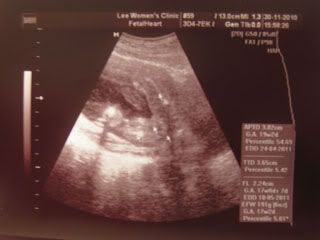

Her tighs and private part.